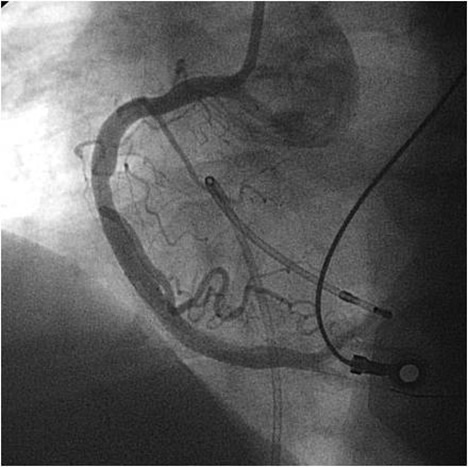

Arterial graft angiography:

For the left IMA angiography, there are two major challenges that need to be overcome. First, wire and catheter advancement into the subclavian artery can be difficult. Older age and peripheral vascular disease are the risk factors for tortuous anatomy. Subclavian stenosis is another cause of difficult subclavian catheterization. In most instances, a JR4 catheter can be positioned into the subclavian artery ostium by counter-clockwise rotation and withdraw of the catheter after positioning it in the ascending aorta. Once the catheter is engaged in the subclavian artery ostium, any manipulation of the catheter has to be performed with extreme caution in order to avoid injury to the subclavian artery and embolism in the territory of vertebral artery. If the catheter advances without any difficulty, it will be reasonable to advance the JR4 catheter and try to engage the left IMA. However, due to steep take off of the left IMA, usually only a non-engaged angiography can be performed using this catheter. It is reasonable to inflated a blood pressure cuff in the left arm and perform a non-selective angiography of the left IMA. In the majority of cases, IMA opacification is satisfactory (Figures 6 and 7). However, for unsatisfactory opacification and when further detail of anatomical information of IMA is needed, a JR4 catheter needs to be exchanged to a left IMA catheter using a long exchange J tip wire. Exchange wire can also be used earlier after subclavian engagement particularly when a JR4 catheter can not be advanced easily. In the majority of cases using left IMA catheter, excellent engagement and angiography of the left IMA can be performed. Again, it is important to avoid extreme manipulations of any catheters in the subclavian artery to avoid any vascular injury and embolism. Contrast injection in the IMA can trigger severe pain in the arm. The patient needs to be warned and informed before injecting the contrast. If subclavian ostial engagement cannot be achieved with a JR4 catheter, a J-wire could be utilized and positioned into the subclavian artery followed by the left IMA or JR4 catheter advancement. There are rare instances when subclavian engagement can not be achieved from femoral arterial route. In such a situation, using the left radial or brachial artery gives direct access into the left IMA ostia. The technique for engaging right IMA is similar to the left IMA. However, right IMA angiography and engagement can be more difficult in dilated aortic root and abnormal steep take off of the right innominate artery. Similar to the left IMA, the right arm can be used in difficult cases. Radial artery graft angiography has the additional challenge of inducing spasm which may require intra-arterial injection of nitroglycerin for appropriate assessment of radial arterial graft size and patency. Aortogram and left ventriculography are usually performed using a pigtail catheter and power injector for the assessment of the left ventricular function, aortic valve regurgitation or missing vein grafts.